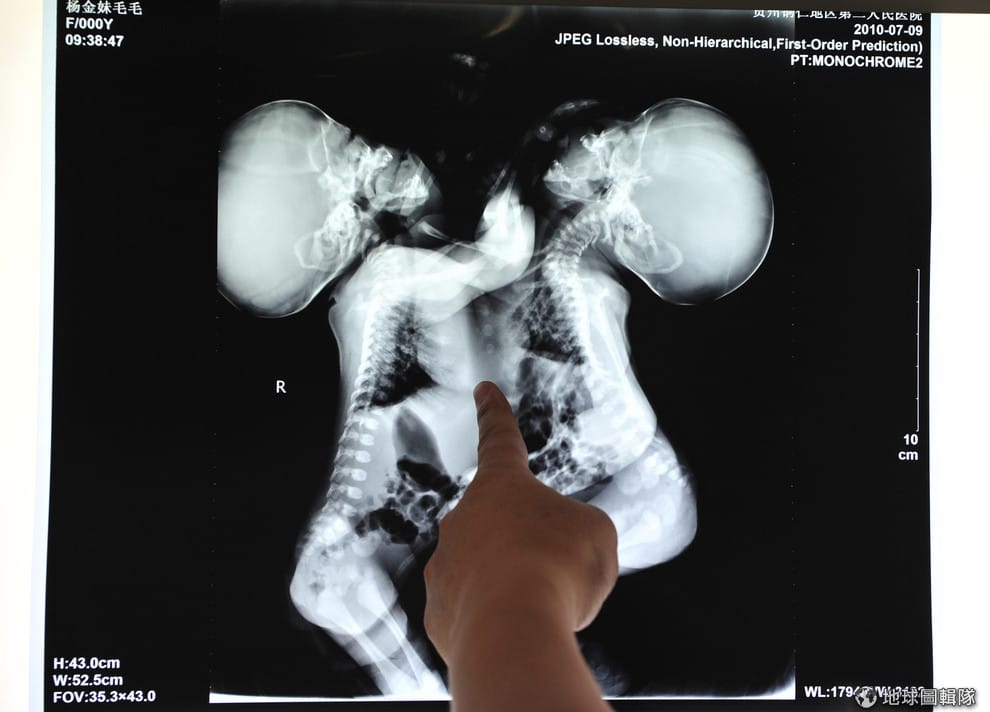

2010年7月的中國,醫療團隊正在針對一對連體姊妹的X光片進行討論,看她們是否適合進行分離手術。